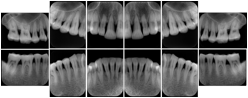

2. A patient requests cosmetic surgery to enhance their facial appearance. The case requires consultation between an orthodontist in New York and an oral surgeon in California. The cephalometric series of 2D projections constructed from a volumetric CT data set that is used for the discussion is arranged by a Structured Display for transfer between the two practitioners.

Cephalometric Series Structured Display

Figure OO-2. Cephalometric Series Structured Display